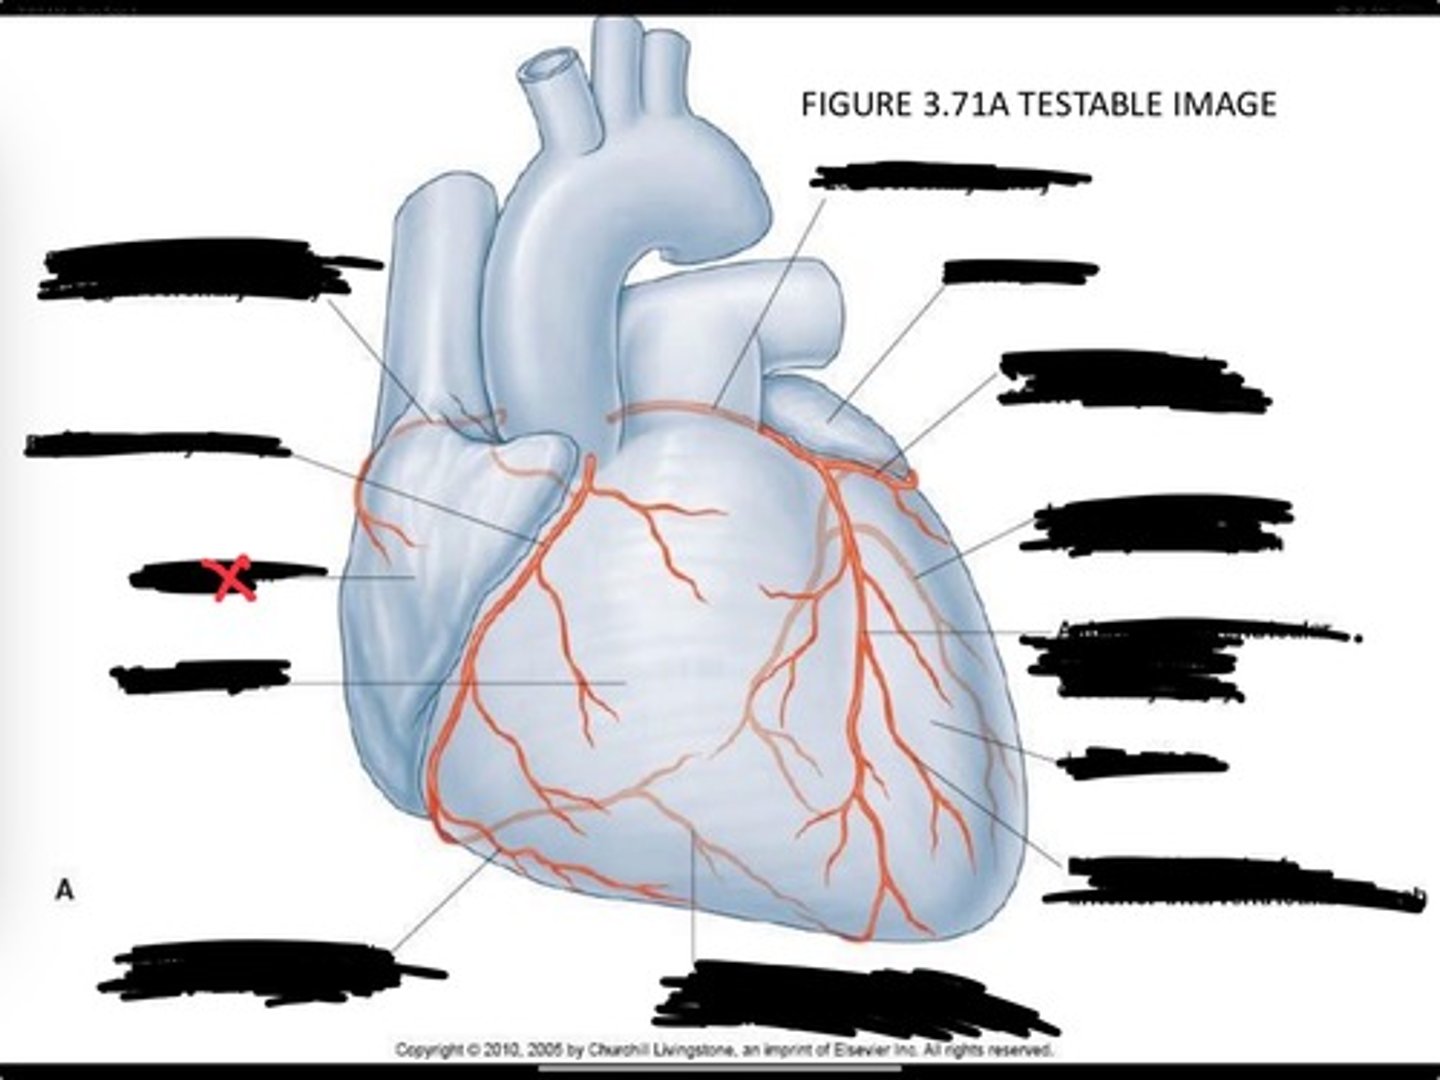

Posterior interventricular branch of right coronary artery

Right arginal branch of coronary artery

Right ventricle

Right atrium

Right coronary artery

Sinu-atrial nodal branch of right coronary artery

Left coronary artery

Left auricle

Circumflex branch of coronary artery